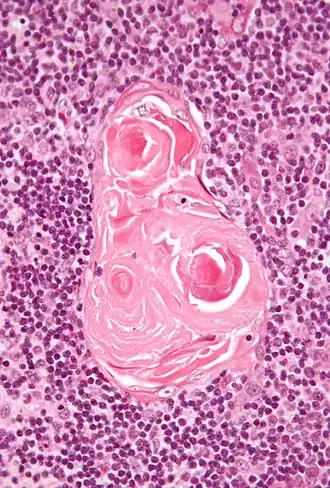

![]() Micrograph of a thymic corpuscle; H&E stain. | |

Hassall's corpuscles (also known as thymic bodies) are structures found in the medulla of the human thymus, formed from eosinophilic type VI thymic epithelial cells arranged concentrically. These concentric corpuscles are composed of a central mass, consisting of one or more granular cells, and of a capsule formed of epithelioid cells. They vary in size with diameters from 20 to more than 100 μm, and tend to grow larger with age.[1] They can be spherical or ovoid and their epithelial cells contain keratohyalin and bundles of cytoplasmic fibres.[2] Later studies indicate that Hassall's corpuscles differentiate from medullary thymic epithelial cells after they lose autoimmune regulator (AIRE) expression.[3] This makes them an example of Thymic mimetic cells.[4] They are named for Arthur Hill Hassall, who discovered them in 1846.[5][6]